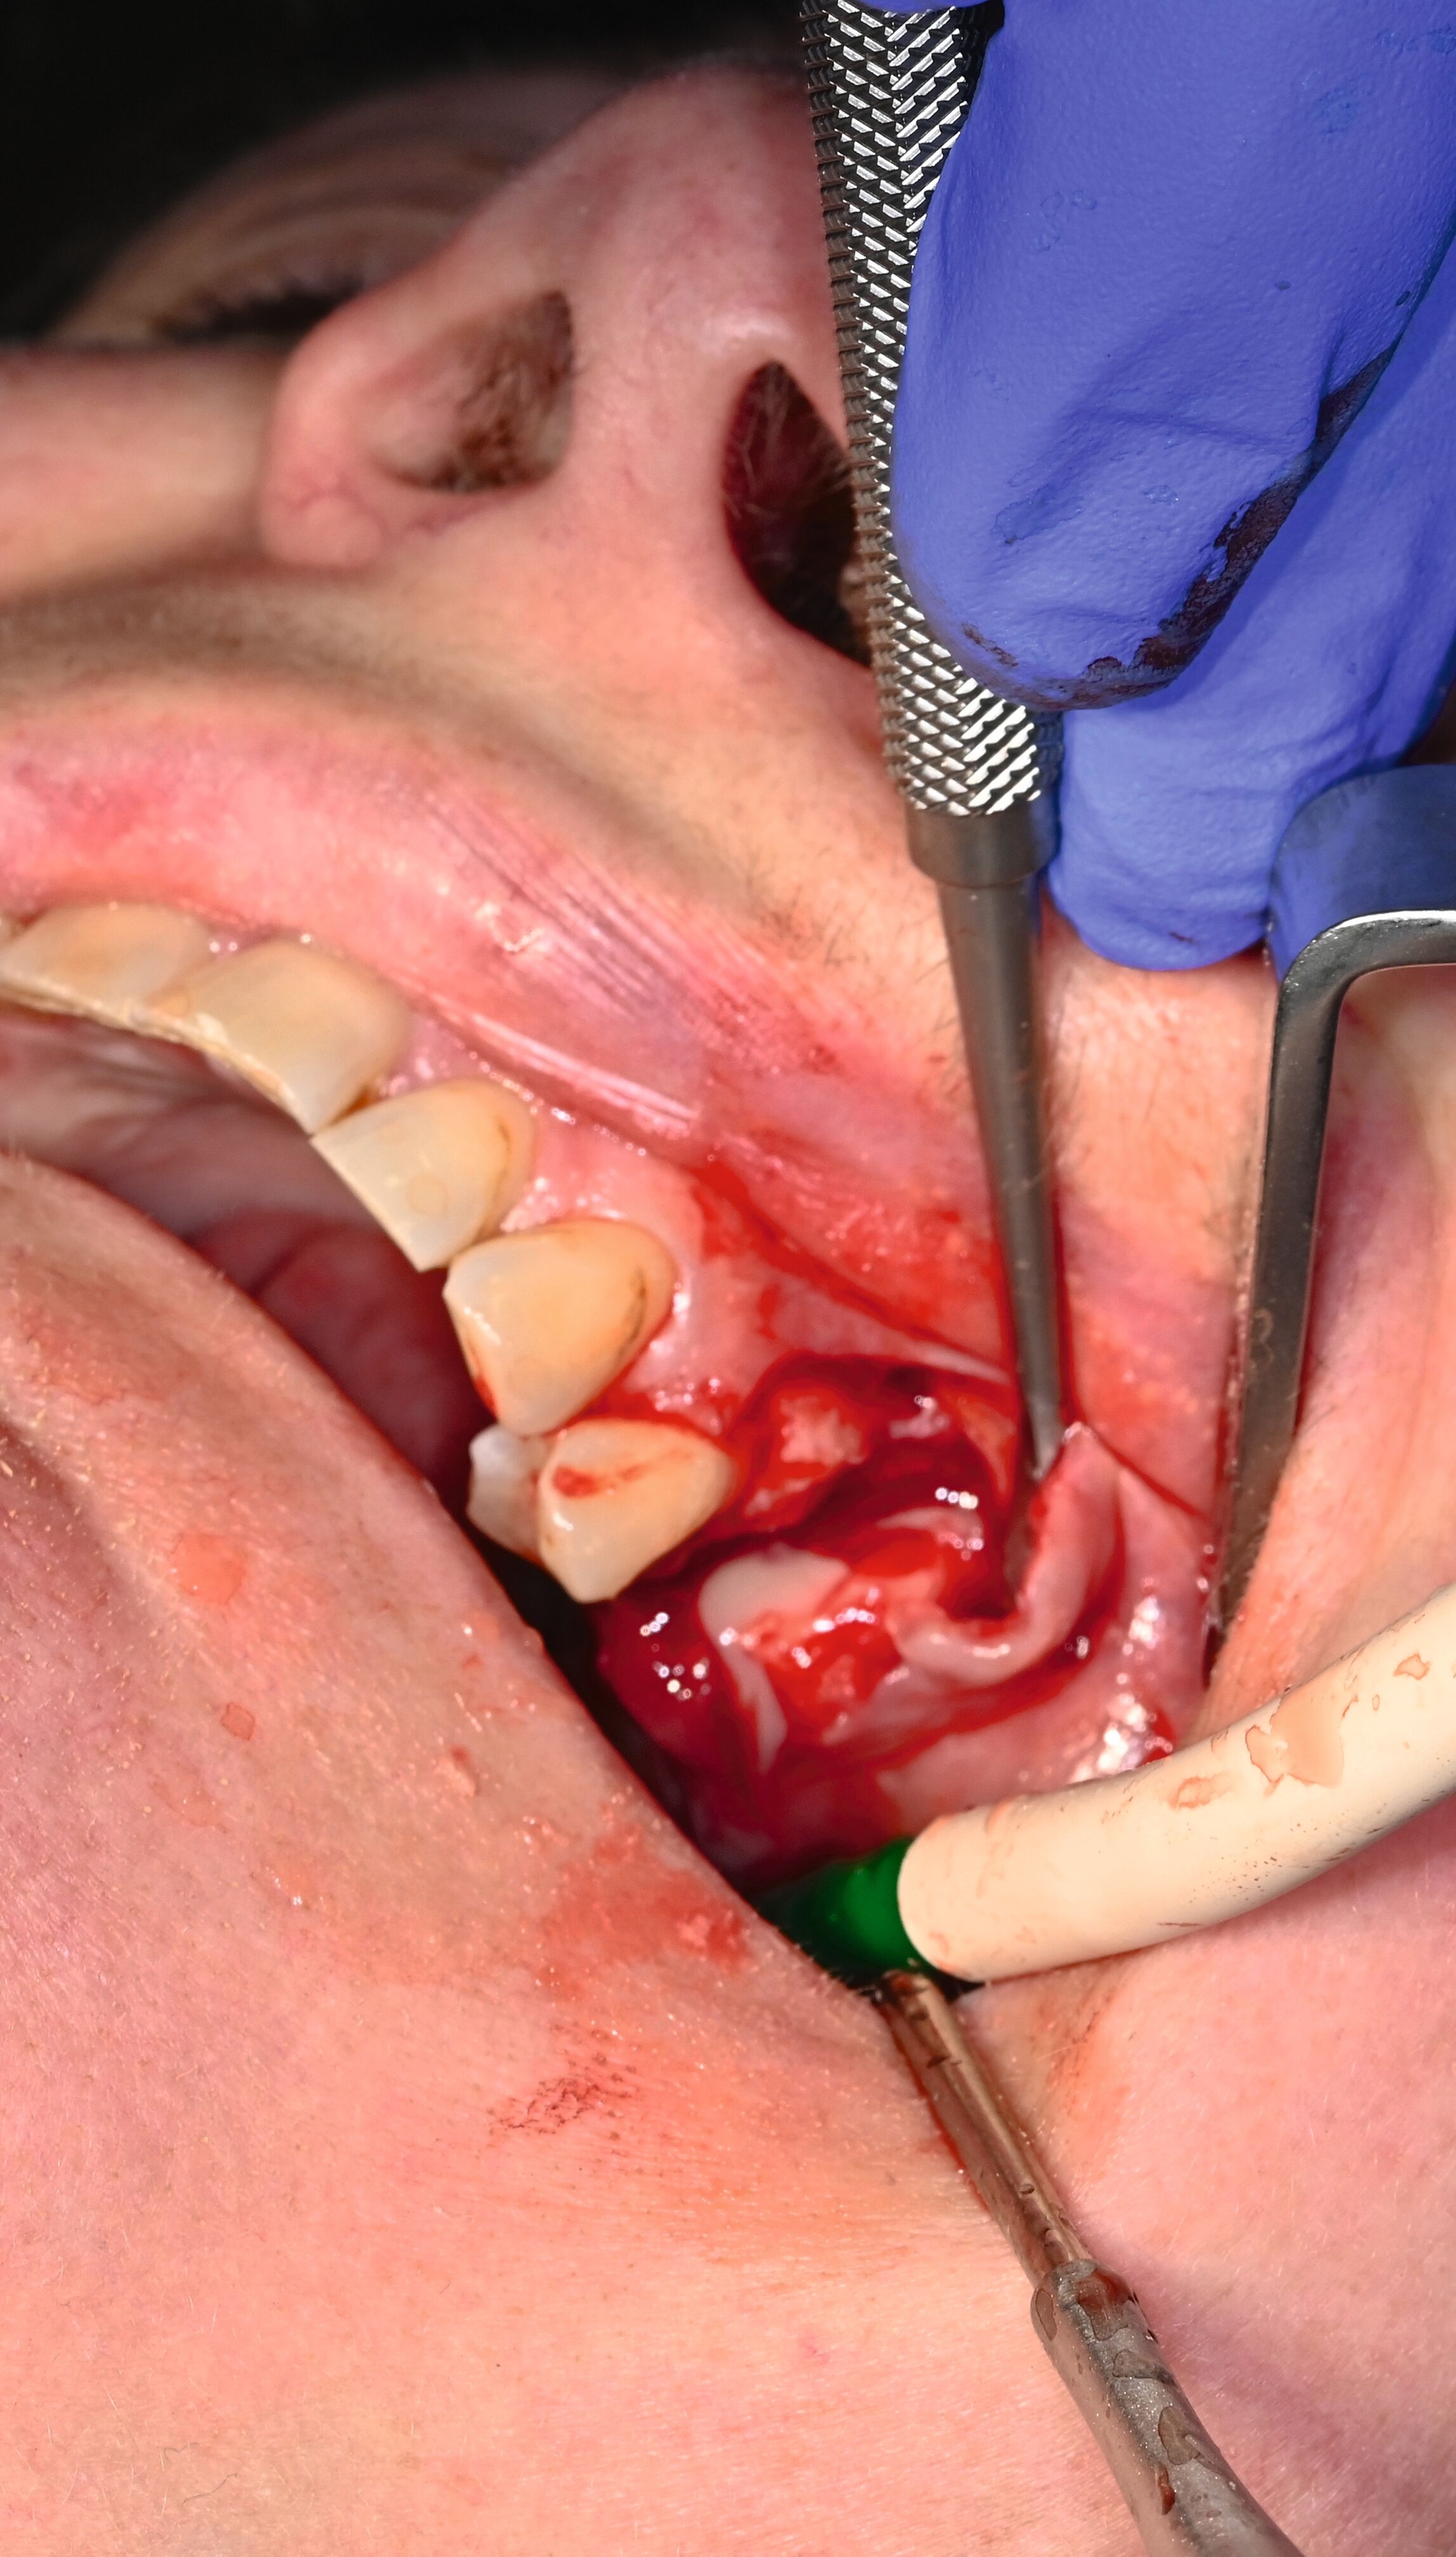

Während der Anmeldungen und Konsilanforderungen wurde notfallmäßig in Lokalanästhesie der in situ verbliebene Wurzelrest 25 mittels Osteotomie entfernt und die Kieferhöhle über die Alveole eröffnet. Das Kieferhöhlenempyem wurde entlastet und ein Drainageröhrchen eingelegt. Es kam zu reichlich Abfluss übelriechenden Eiters (Abbildung 5) und zur merklichen Entlastung für die Patientin. Es wurden Abstriche für die mikrobiologische Untersuchung genommen und die Kieferhöhle wurde wiederholt mit NaCl gespült.